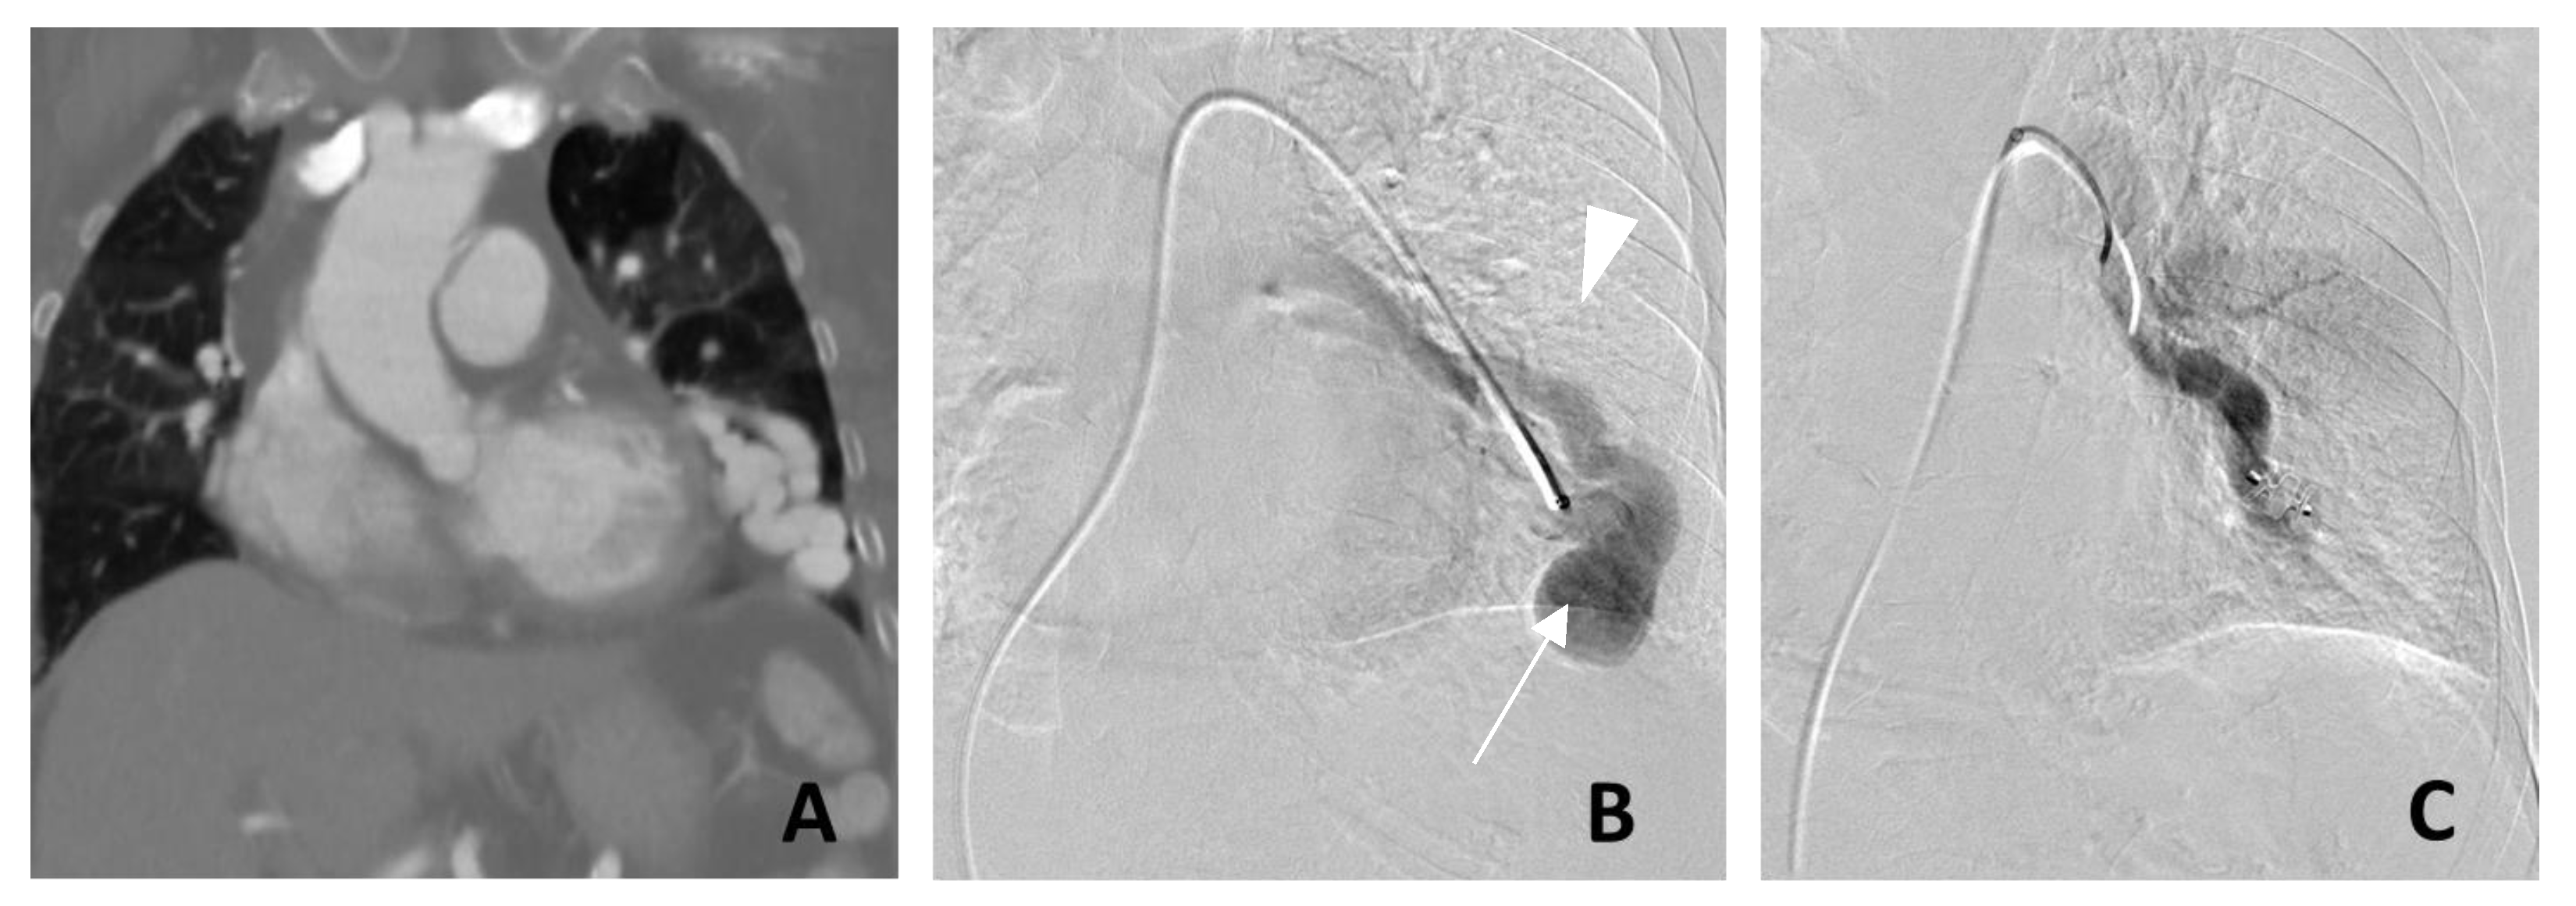

- (1)

3. Management of PAVM